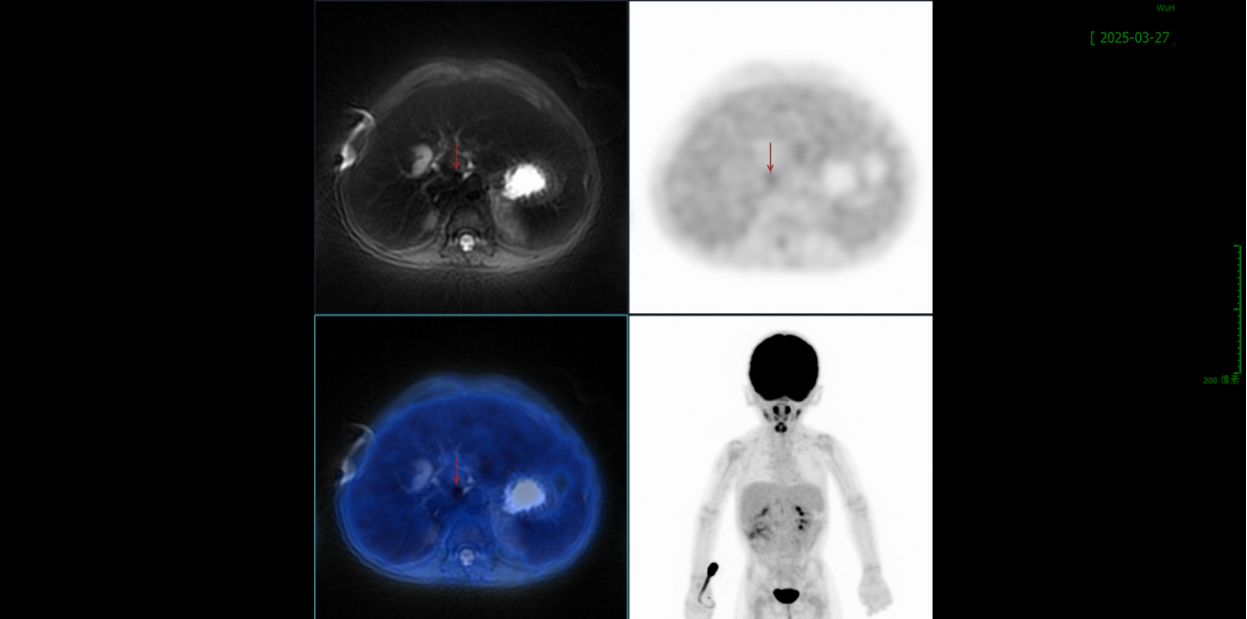

2025.03.27(第5周期中)

PET/CT:约平Th11椎体水平腹主动脉有异常信号,代谢轻度增高,1.0×0.9cm,右侧膈肌脚稍增粗,代谢不高,较前次病灶形态缩小,代谢程度减低;右侧肾上腺未见明确显示;以上考虑恶性肿瘤综合治疗后活性受抑制。疗效评价:CR。